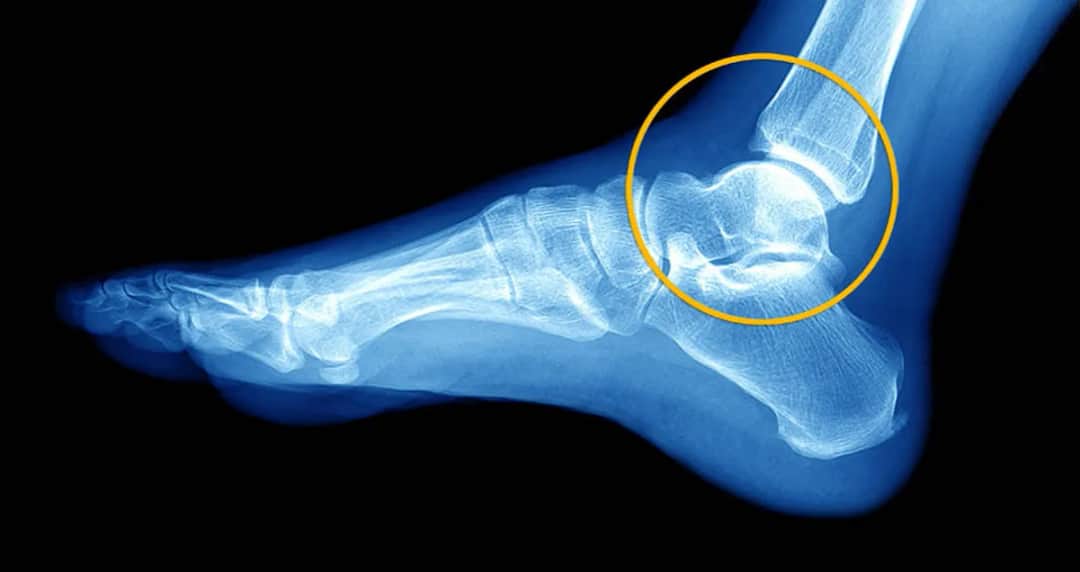

Jak opisać skręcenie stawu skokowego dla PZU? Maksymalizuj odszkodowanie!

Skręcenie stawu? Zrozum objawy, stopnie urazu i protokół PRICE. Dowiedz się, kiedy iść do lekarza oraz jak skutecznie leczyć i zapobiegać nawrotom!